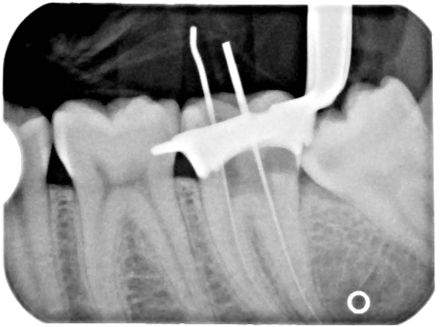

Xray of a Root Canal Operation

Xray of a Root Canal Operation — Image from Wikipedia